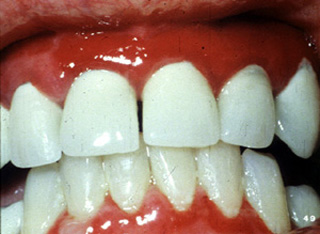

Este paciente, es una mujer mexicana de 49 años de edad que  presentó ulceraciones orales por un período de un año. Se trató sin éxito con corticoides en varias ocasiones. La biopsia no determinó un diagnóstico.

Durante la anamnesis ella había tomado un diurético, para el tratamiento de la  hipertensión durante los últimos cinco años. Cuando se cambió el diurético y se administró corticoides  el problema se resolvió en poco tiempo. La terapia antihipertensiva es obviamente una de las causas primarias del la erupción liquenoide necrotizante.